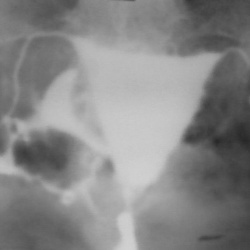

Барышня, 25 лет, обследуется по направлению гинеколога.Что скажете?

Молодая женщина 28 лет. 5 лет назад - внематочная беременность, частичная резекция трубы слева.В апреле 2011 года - метросальпингография для оценки состояния труб.Ваше мнение, коллеги?